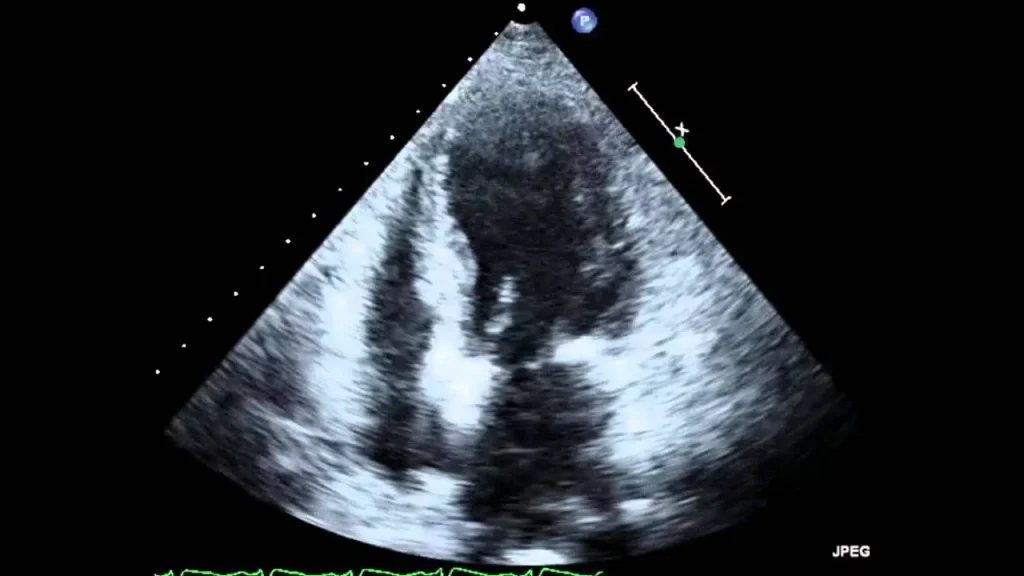

اکو قلب جنین یا Fetal Echocardiography نوعی سونوگرافی تخصصی است که به پزشکان امکان میدهد ساختار و عملکرد قلب جنین را در دوران بارداری با دقت بالا بررسی کنند. در این روش، دستگاههای پیشرفته با استفاده از امواج فراصوت تصویری دقیق از قلب، بطنها، دهلیزها، دریچهها، عروق اصلی و حتی ریتم قلب جنین ایجاد میکنند. به همین دلیل، اکو قلب جنین یکی از ابزارهای حیاتی برای تشخیص زودهنگام مشکلات قلبی محسوب میشود.

- کیفیت تجهیزات: دستگاههای پیشرفته با قابلیت Doppler و تصویربرداری سهبعدی دقت تشخیص را بسیار افزایش میدهند. به همین دلیل مراجعه به بهترین مراکز اکو قلب جنین اهمیت زیادی دارد.